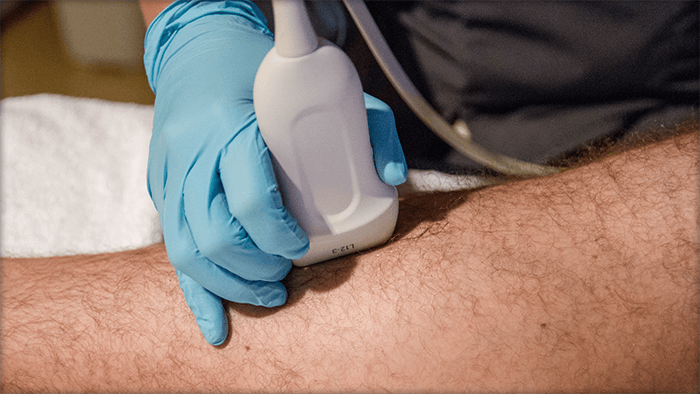

Diagnostic Procedures Superficial venous problems may be visible on the legs, but it is important to let a doctor confirm a diagnosis. Sometimes SVI can be indicative of other problems in the deep veins, such as deep venous obstruction and a doctor will need to determine if it is DVO or SVI. To confirm SVI, and to locate the source of insufficiency, a doctor may use a combination of physical exam, medical history and one or more of the following tools:5 Photos of Diagnostic Procedures

Videos of SVI Diagnostic Procedures

Duplex Ultrasound

This is a non-invasive test which uses sound waves to create a color map of the blood vessels and examines blood flow in your legs.